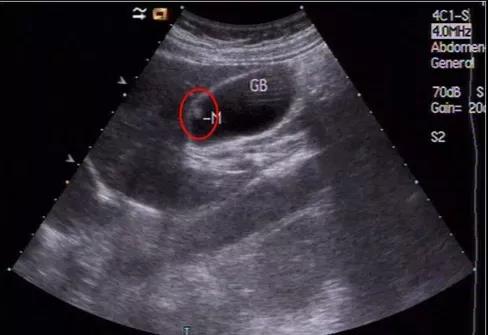

①看真假:真正可能變癌的是真息肉,假息肉不用管;

②看大小:長到1厘米了就需要考慮手術(shù),風(fēng)險(xiǎn)大了;